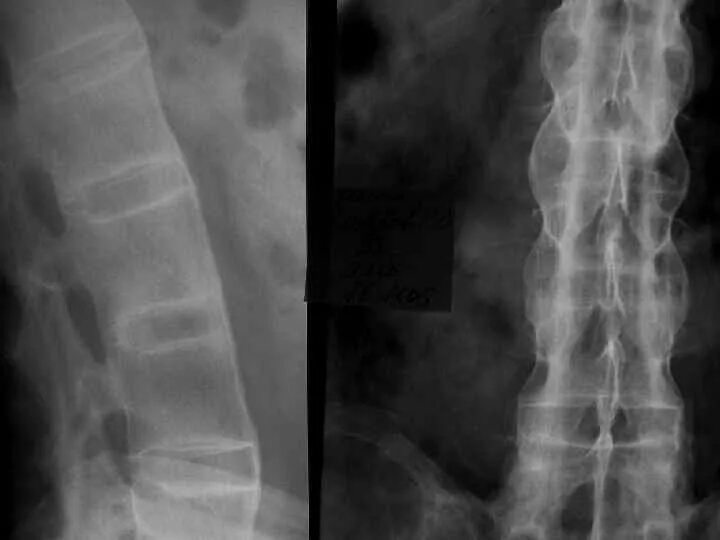

Бехтерева анкилозирующий спондилоартрит